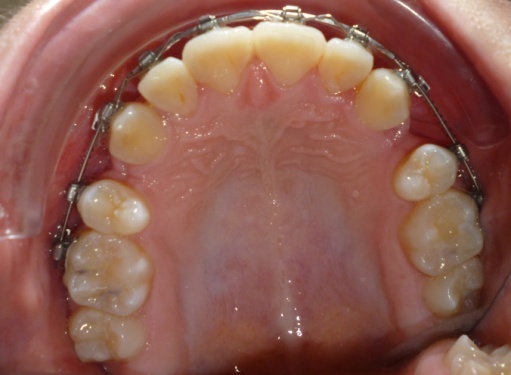

2 - Alignement par brackets autoligaturants

Le recul progressif des dents encombrées dans les espaces d’extraction créés à cet effet a été rendu possible grâce à l’utilisation de brackets autoligaturants, particulièrement efficaces pour respecter l’angulation et le torque des dents. Tous les espaces d’extraction ont été exploités pour résoudre l’encombrement, évitant ainsi tout recul des dents antérieures. L’occlusion obtenue est physiologique, en classe I canine et en classe II molaire thérapeutique.